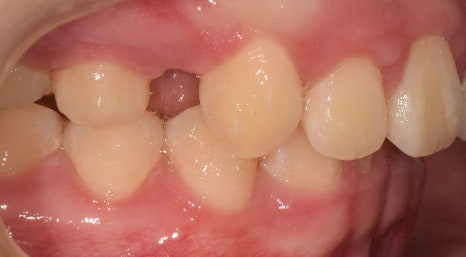

처음에는

치아가 보이지 않을 정도로

많이 튀어나왔지만,

턱이 뒤로 들어가면서

올바른 형태로 찾아갈 수 있었습니다.

그러나,

아래쪽 치아가 부족한 관계로

그만큼 뒤쪽으로 밀어 넣어야 했기 때문에

위쪽에 있던,

‘작은 어금니’를 뽑고 나서

인비절라인을 함께 병행하기로 했는데요.

현재까지,

교정 치료를 진행 중에 있으며

점차 제 위치를 찾아가고 있습니다.